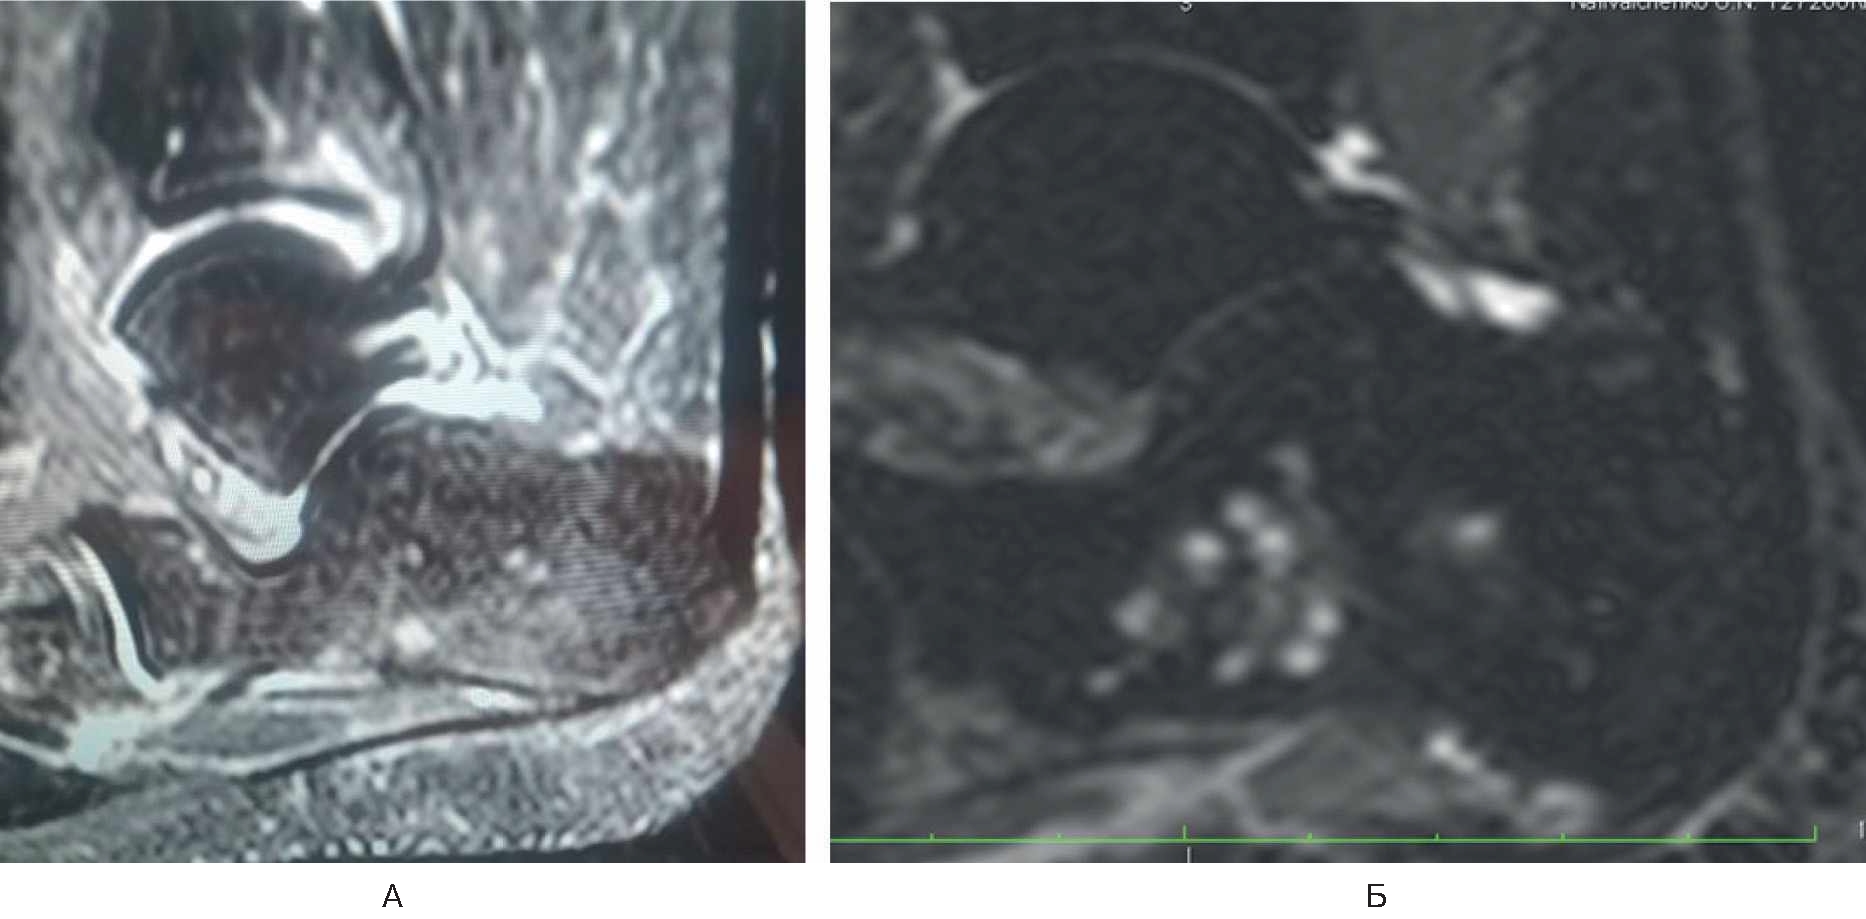

Спустя 6 мес стала отмечать боль (8 баллов по ВАШ) в области нижнего полюса надколенника в покое и при нагрузке, резкую боль – в нижнем полюсе надколенника при активном и пассивном сгибании в коленном суставе. Обратилась в травматолого-ортопедическое отделение. Семейный и соматический анамнез не отягощен. В феврале 2022 г. провели МРТ коленного сустава, обнаружен асептический некроз нижнего полюса надколенника (рис. 2). Выполнена артроскопия коленного сустава с декомпрессией очага некроза.

Рис. 2. МРТ коленного сустава у пациентки Б. Диагноз – асептический некроз нижнего полюса надколенника.

В раннем послеоперационном периоде пациентка отмечала снижение боли (интенсивность – 3 балла по ВАШ). Назначены терипаратид подкожно 20 мкг 1 раз в сутки в течение 2 мес и ношение ортеза на коленный сустав. На контрольный осмотр не явилась.

Лечилась у невролога консервативно с мая по сентябрь 2021 г. без положительной клинической динамики, а с сентября по декабрь 2021 г. – у травматолога по месту жительства по поводу тендопатии. Положительной клинической динамики не было. В марте 2022 г. на приеме у ортопеда выполнена МРТ правой стопы, диагноз – асептический некроз тела пяточной кости (рис. 4А).

Рис. 4. МРТ правой стопы у пациентки Г.

В марте 2022 г. произведена транскутанная остеоперфорация тела правой пяточной кости. Назначен терипаратид 20 мкг подкожно 1 раз в сутки. МРТ-контроль через 1 мес. На контрольном осмотре: пациентка отмечает восстановление функции правой нижней конечности, отсутствие болевого синдрома в правой пяточной кости (0 баллов по ВАШ). По данным контрольной МРТ – положительная динамика, отсутствуют признаки асептического некроза (см. рис. 4Б).

А – асептический некроз тела пяточной кости; Б – отсутствие признаков асептического некроза.